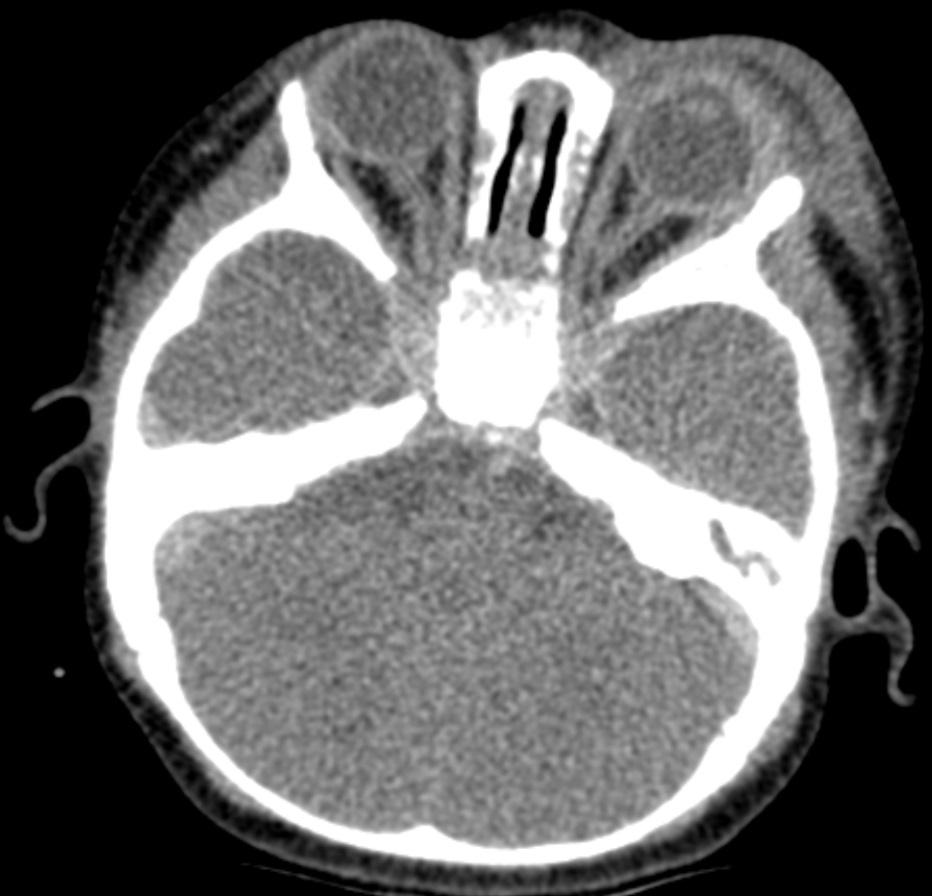

Een zuigeling wordt door de huisarts met spoed naar de kinderarts verwezen vanwege sinds een dag bestaande koorts en een progressieve zwelling van het linker ooglid. Ook is er wat purulente uitvloed.